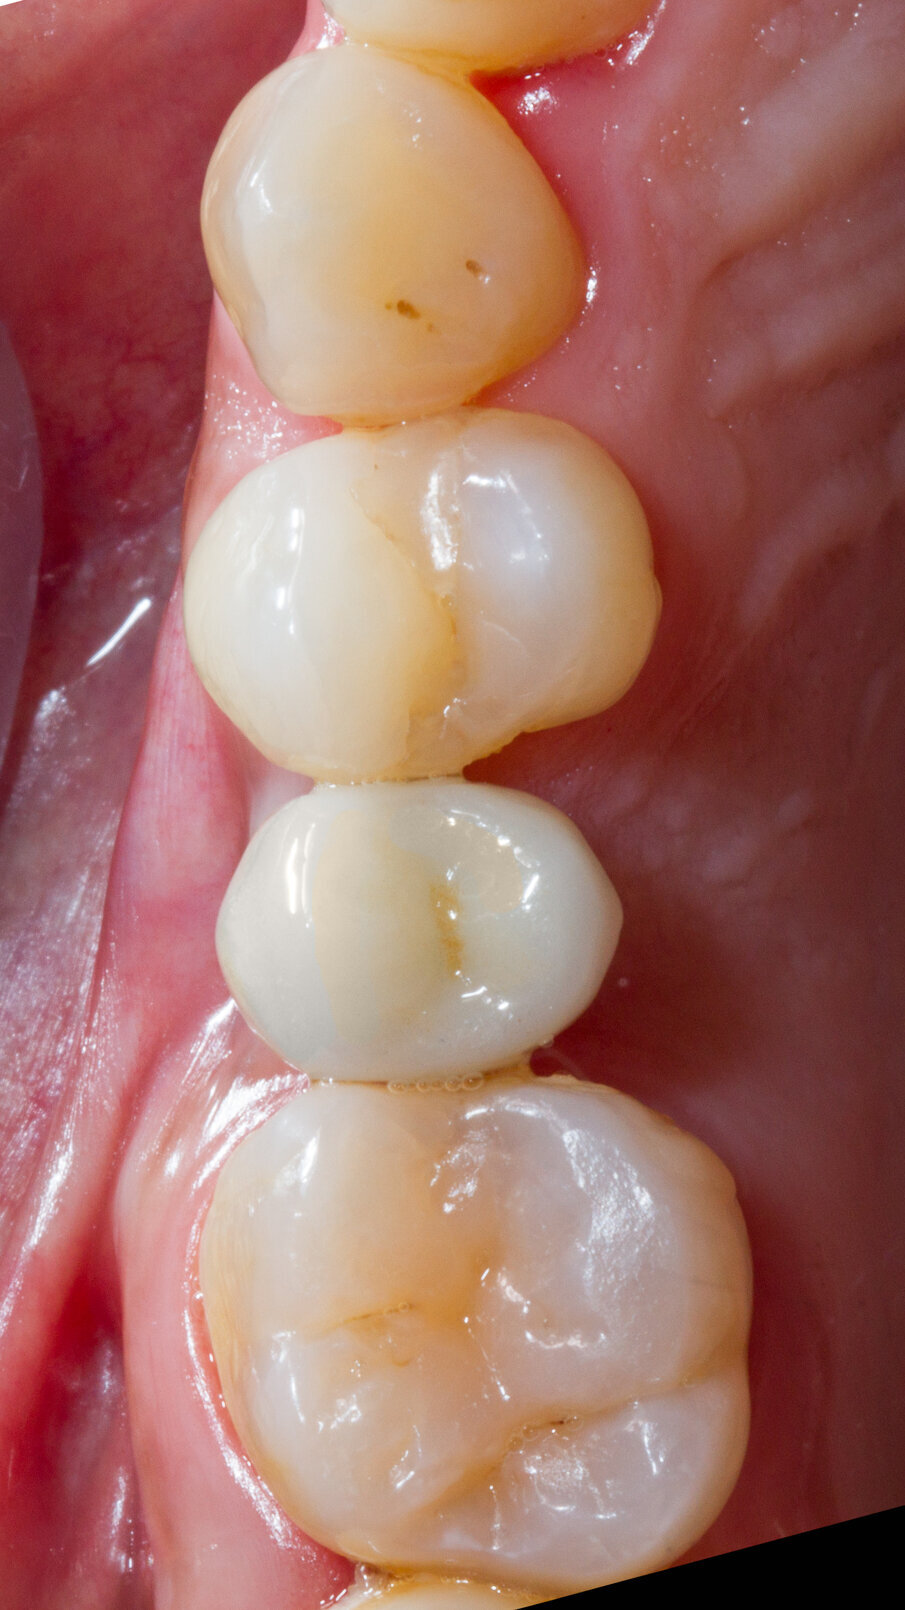

Caso clinico Viene presentato un caso clinico di GBR per la ricostruzione volumetrica di una cresta ossea atrofica mascellare con inserimento di biomateriale osseo di natura eterologa (OsteoBiol Gen-Os) e di una lamina corticale soft collagenata (OsteoBiol Lamina Soft) stabilizzata sulla sede del difetto osseo con utilizzo di colla di fibrina (Tisseel, Baxter) e con 2 chiodini di fissazione crestali. La paziente N.H. di anni 42, sesso femminile, non fumatrice, ASA 1, si presentò alla mia osservazione per la sostituzione di un elemento dentale, 2° premolare superiore destro, estratto più di 15 anni prima (Figg. 2, 3). Dall’esame clinico si osserva un marcato riassorbimento in senso orizzontale del sito edentulo, lo stato dei tessuti gengivali è di salute, non vi sono lesioni parodontali sui denti contigui. L’esame CBCT conferma la perdita di oltre il 50% del tessuto osseo vestibolare pur rimanendo conservata l’altezza verticale della cresta (Fig. 4).

Fig. 2 - Situazione iniziale.

Fig. 3 - Situazione iniziale. Vista occlusale.